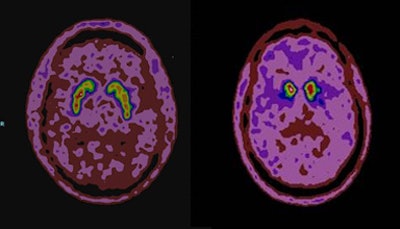

| F-18 DOPA-PET images of a patient without Parkinson's disease (left) and a patient with the disease (right). The left image shows symmetric homogenous uptake of the radiotracer throughout the striatum. The right image shows absent radiotracer uptake to the posterior striatum with still preserved activity in the anterior part of the striatum. Image courtesy of Dr. Joanna Kusmirek. |

Parkinson's disease is caused by the loss of the neurotransmitter dopamine in the brain. Dopamine stimulates movement, cognition, and memory, and helps neurons connect and communicate in the basal ganglia. Functional imaging of the dopamine deficiency can be done using F-18 DOPA-PET as a marker of dopamine activity.

An analysis of the 28 scans revealed 20 true-positive results and seven true-negative results. There was one false negative and no false positives. Based on the results, the researchers calculated the sensitivity for DOPA-PET at 95.4%, specificity rated 100%, positive predictive value also was 100%, and negative predictive value was 87.5%.